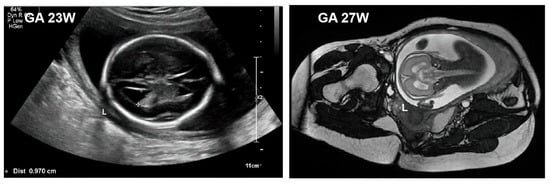

2.3. Accessory Examination

| Macrocephaly, fetal overgrowth | Macrocephaly, overgrowth |

| Polyhydramnios | Severe lung lesions |

| Central nervous system abnormalities | Ventricular dilatation, hypoplasia, agenesis of the corpus callosum, mega cisterna magna |

| Renal abnormalities | Cardiac anomalies (including PDA, ASD, and ventricular septal defect) |